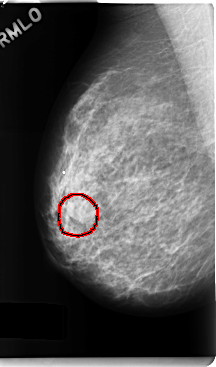

FILE: C_0248_1.RIGHT_MLO.OVERLAY

TOTAL_ABNORMALITIES 1

ABNORMALITY 1

LESION_TYPE MASS SHAPE LOBULATED MARGINS MICROLOBULATED

ASSESSMENT 4

SUBTLETY 5

PATHOLOGY BENIGN

TOTAL_OUTLINES 1

BOUNDARY